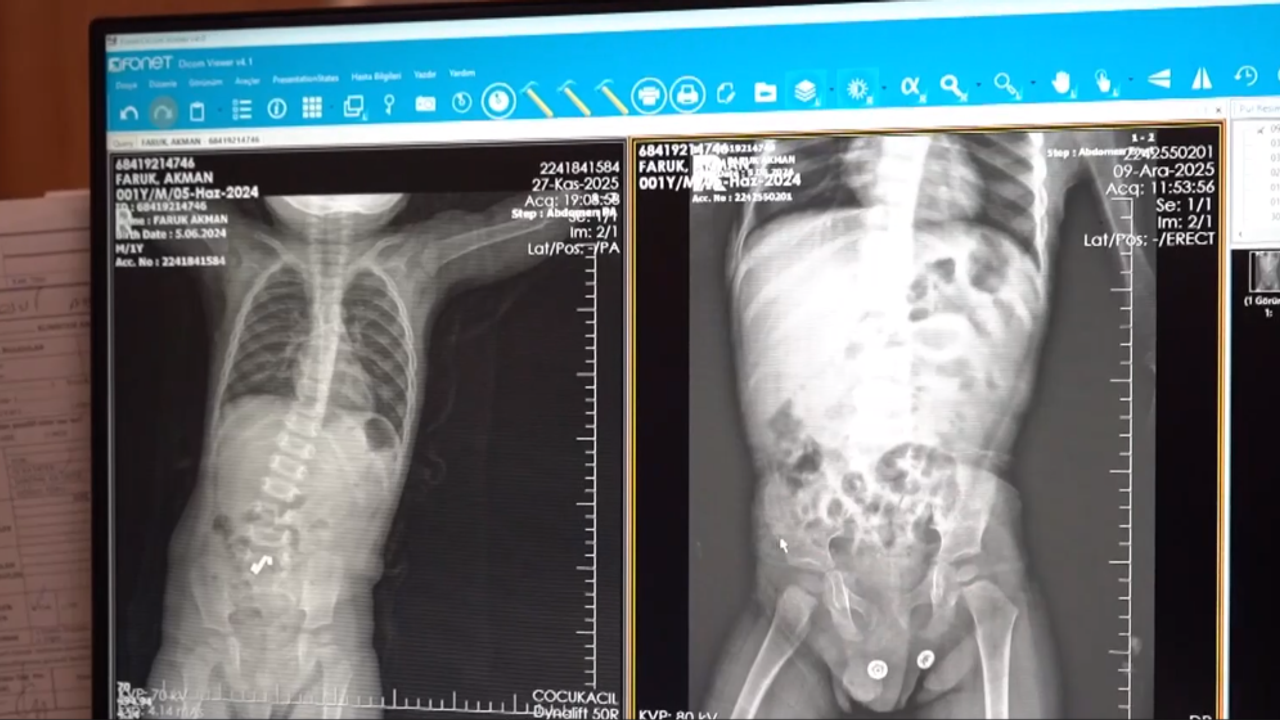

Batman Eğitim ve Araştırma Hastanesi'nden yapılan açıklamaya göre, ailesi tarafından acil servise getirilen 1,5 yaşındaki Faruk Akman'ın yapılan tetkiklerinde bağırsağında 3 mıknatıs olduğu belirlendi.

Çocuk Cerrahi Uzmanı Op. Dr. Mücahit Erman tarafından gerçekleştirilen operasyonla Akman'ın bağırsağından ikisi 5 milimetre, biri yaklaşık 2 santimetre olan mıknatıslar çıkarıldı.